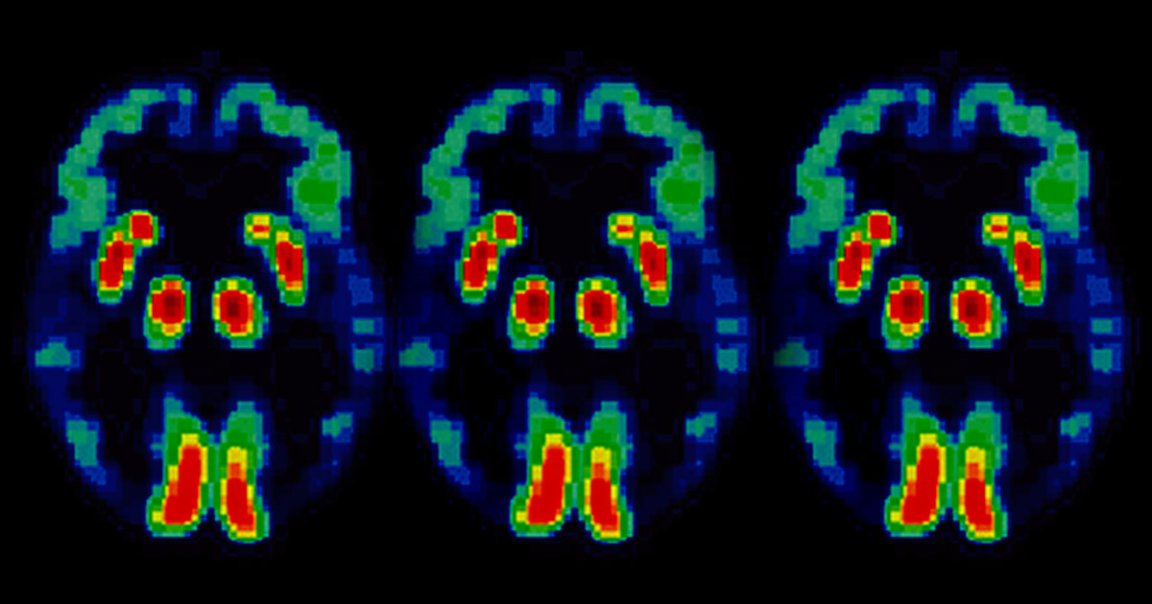

A new nationwide clinical trial is currently recruiting people with Alzheimer’s disease to see if a new drug can halt or slow down memory loss and other symptoms.

The trial, called “T2 Protect AD,” involves 48 weeks of treatment and monitoring. Subjects will receive either a placebo or a drug called troriluzole, which has been shown to slow down the rate at which brain cells die off, according to WGME — and if it’s successful, the trial could chart a new course for dementia treatment.